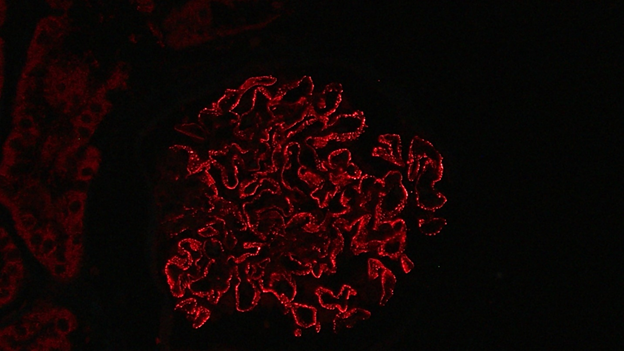

NELL1 co-localizes with IgG within glomeruli, confirming the results of protein G immunoprecipitation from kidney biopsy tissue. 6/21

Histologically, NELL1 MN cases have prominent capillary loops with formation of spikes and holes on silver stains as we would expect. There were no proliferative changes, such as those seen in lupus nephritis. 7/21

What sets NELL1 apart is that there is segmental to incomplete global IgG staining on immunofluorescence. This allows us to pick out these cases from other membranous cases. 8/21